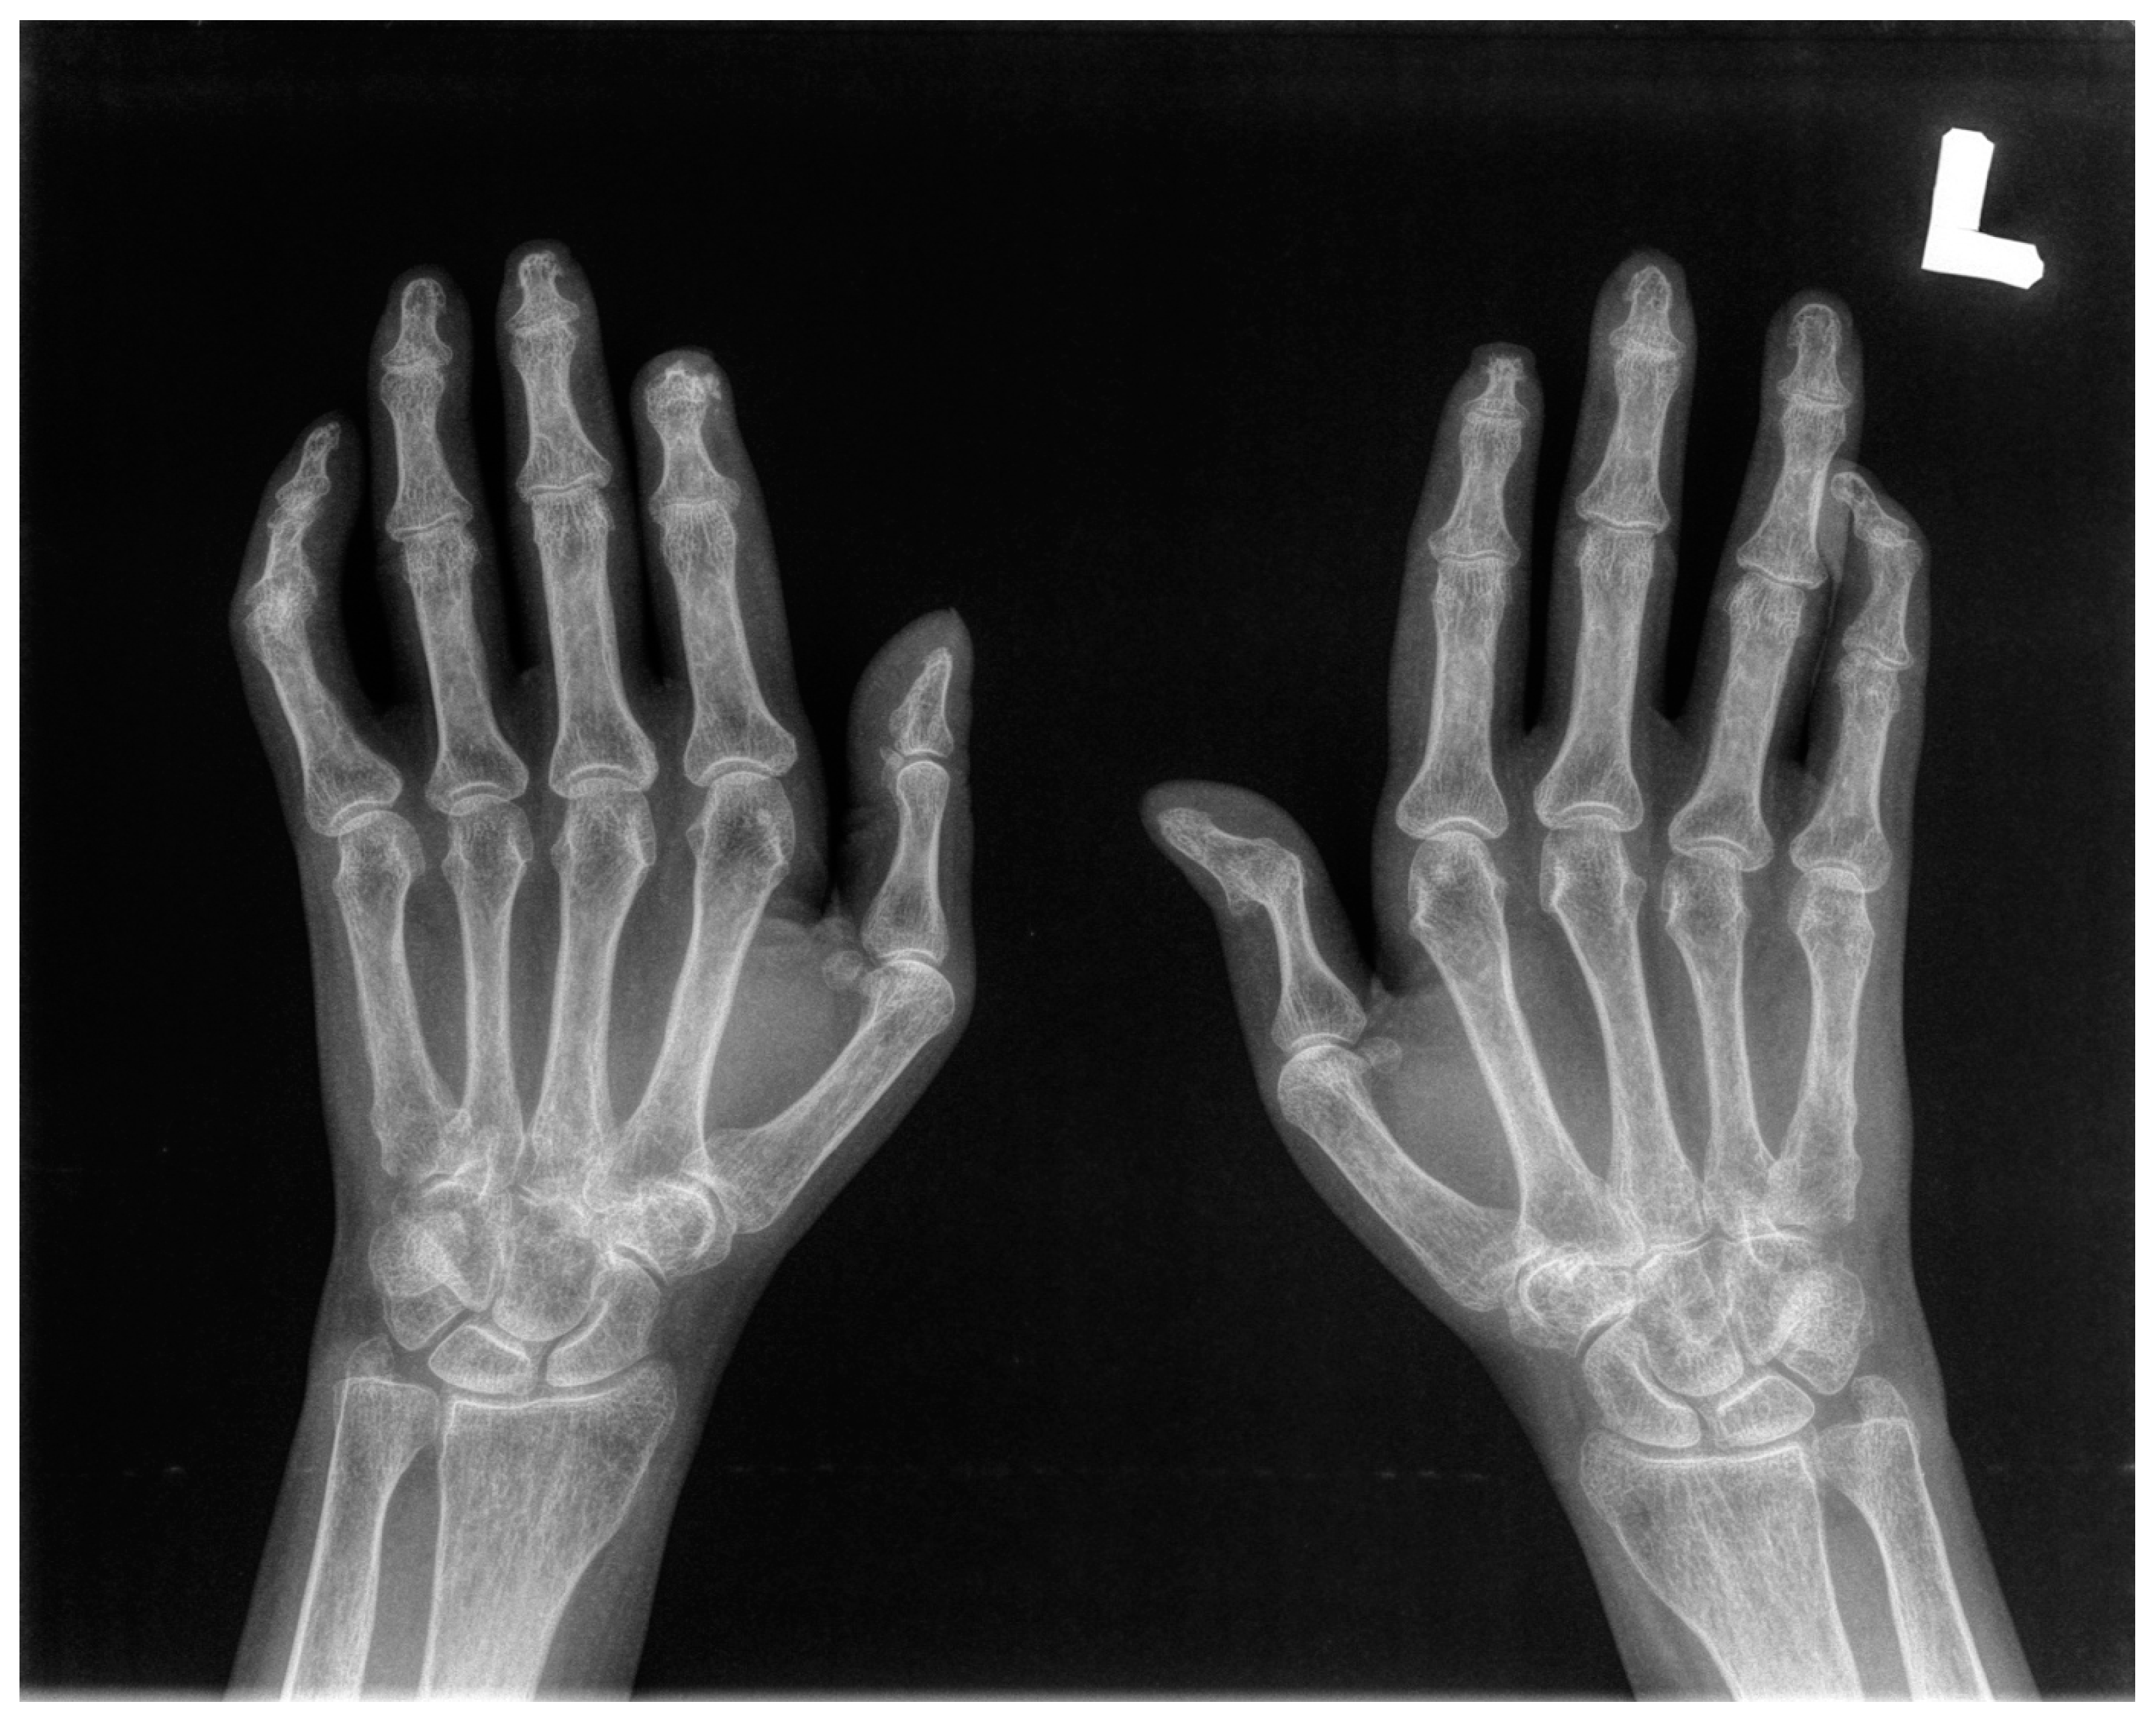

The X-ray examination of both hands was conducted in all participants (Figure 2).

Figure 2.

Radiological manifestations of pathological changes in the hands in SSc patients’: Resorption of bilateral 2nd distal phalanxes and 1st phalanx of the right hand (acro-osteolysis); joint space narrowing of PIP and DIP joints; erosions and juxta-articular osteopenia; calcinosis of the 2nd fingertip.

Ten SSc patients with mean age 62.6 (range 57 to 71) were included in the study. Nine of them were female. Seven patients suffered from a limited form of SSc (lcSSc). Six patients presented gastrointestinal manifestations. Four patients demonstrated pulmonary fibrosis. Six patients showed cardiac abnormalities. One of them presented renal pathological involvement. Detailed characteristics of the patients are provided in Table 1. All the patients had clinical signs of hands arthralgia. On clinical examination, we found signs of acro-osteolysis confirmed by X-ray in four patients. Three patients manifested the symptoms of digital ulcers; two of them had signs of calcinosis of distal phalanx (Table 1). The X-ray examinations of both hands were conducted in all ten patients. They revealed osteolysis of proximal and distal phalanxes (acro-osteolysis), joint space narrowing of DIPJs and PIPJs, erosions and juxa-articular osteopenia, as well as calcinosis of the fingertips (Figure 2). Ten healthy volunteers were included in the study as a control group. There were no statistically significant differences between both groups in terms of age and gender.